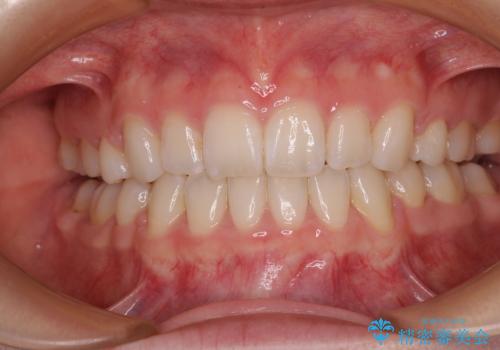

矯正治療が終わるタイミングに合わせてインプラントの埋入を行っていたので、矯正治療を終了すると同時にセラミック補綴治療を行えました。

短期間でしっかりと治療を終えることができました。